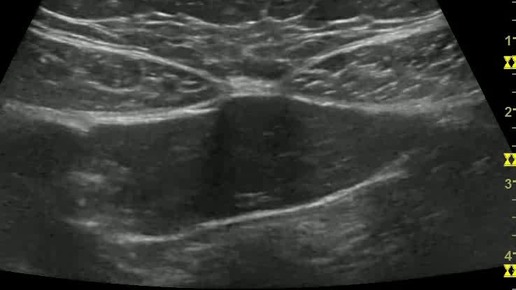

Видео к статье "Ультразвуковая анатомия передней брюшной стенки"Адрес: https://dzen.ru/a/Z0A_0oqqNWBzirBD